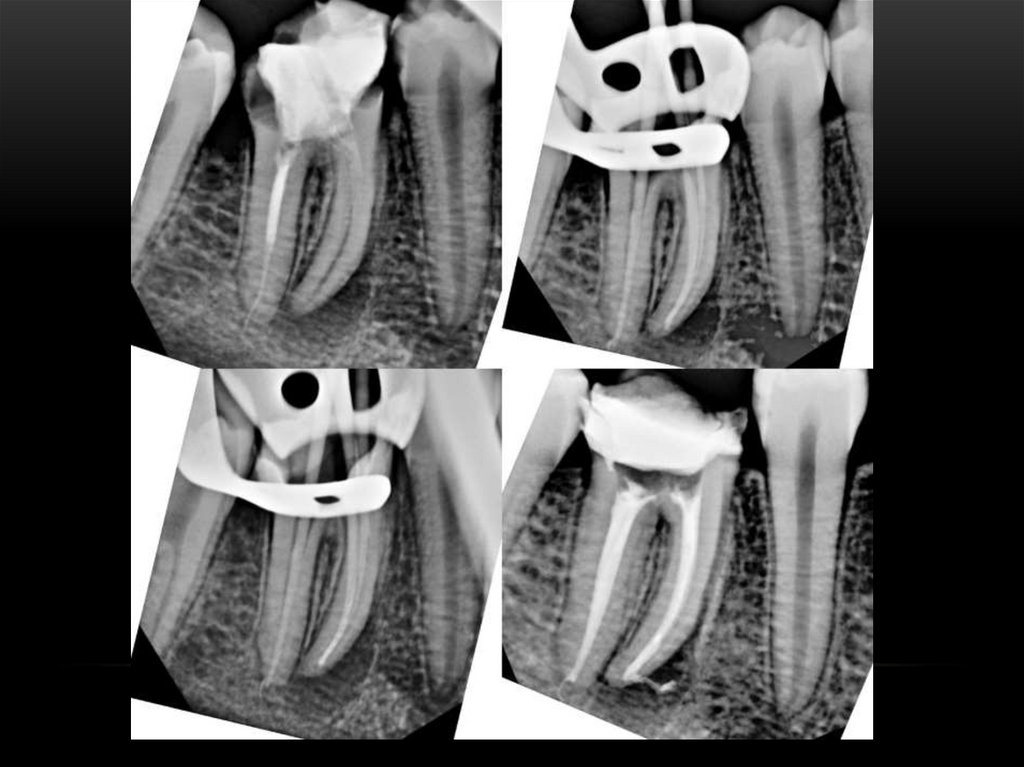

Лечение корневых каналов